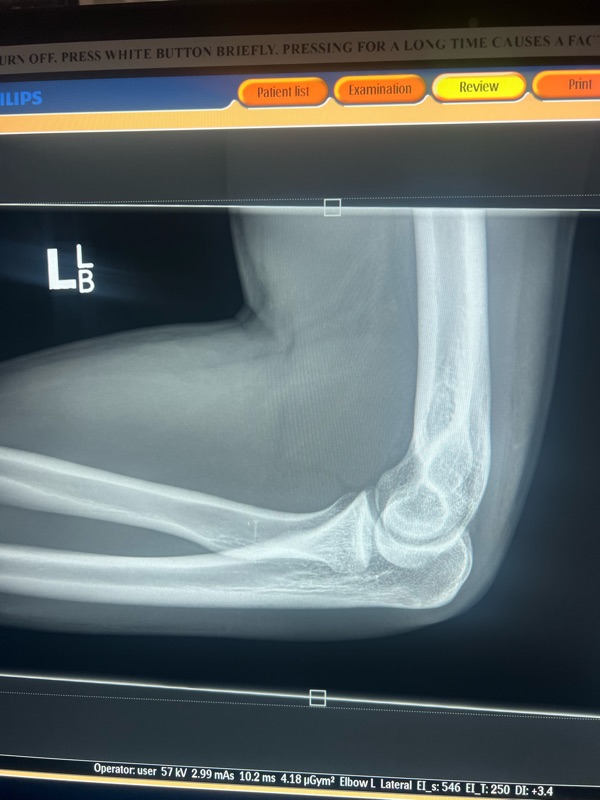

it ended like this! Not amazing but luckily nothing broken. A couple of hours at Mansfield hospital. We left had dinner and met Andrew and Luce at the camp ground and camped the night. Harry was pretty disappointed he didn’t get to race but one’s still a nice weekend away.

Ended like this…